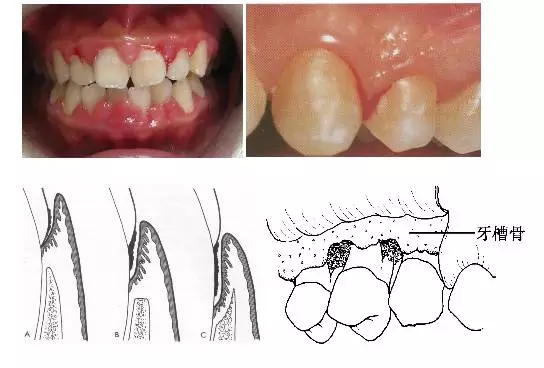

1、牙齦改變:正常牙齦粉紅色、菲薄而緊貼牙面,附著齦有點彩?;佳例l炎時游離齦和齦乳頭呈鮮紅或暗紅色,齦緣變厚,齦乳頭圓鈍,不再緊貼牙面;由于結(jié)締組織內(nèi)炎性浸潤及膠原纖維消失,使原來致密堅韌的牙齦變得松軟脆弱,缺乏彈性;同時由于牙齦腫脹或增生,齦溝深度增加,但上皮附著水平仍位于正常的釉牙骨質(zhì)界,即出現(xiàn)假牙周袋。

3、牙周袋形成:牙周袋是病理性加深的齦溝,是牙周炎最重要的病理改變之一。按照袋底的位置,可將牙周袋分為骨上袋和骨下袋;按牙周袋累及牙面的情況可將其分為單面袋、復(fù)合袋、復(fù)雜袋。

4、牙槽骨吸收:牙槽骨吸收是牙周炎的另一個主要病理變化,由于牙槽骨的吸收,使牙齒的支持組織喪失,牙齒逐漸松動,最終脫落或拔除。牙槽骨的吸收可分為水平吸收、垂直吸收、凹坑狀吸收等幾種類型。

5、牙齒松動和移位:由于牙周炎使牙槽骨吸收,牙周支持組織減少是牙齒松動的最主要原因;另外在咬頜創(chuàng)傷合并有牙周炎時,也可造成牙齒松動。由于患有牙周炎的牙齒缺乏牙周支持組織,所以,在咬頜創(chuàng)傷的不良咬頜力作用下,牙齒可出現(xiàn)病理性移位。